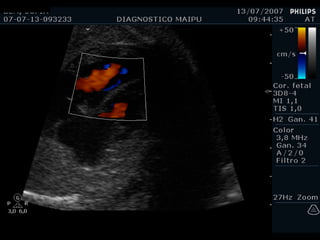

ECOCARDIOGRAFIA FETAL Modo B Modo M Doppler ¿CUANDO? A partir de la sem 12 por vía TV A partir de la sem 18 por vía abdominal Optimo: semana 22

EXAMEN BASICO EXTENDIDO Corte de 3 vasos Tracto de salida izquierdo Tracto de salida derecho